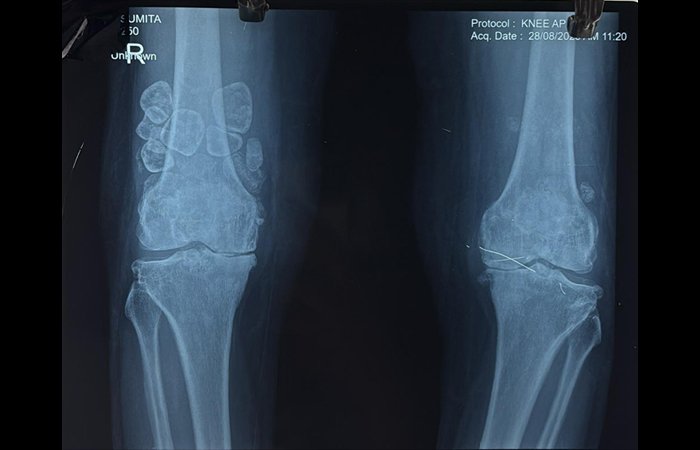

સામાન્ય રીતે લોકોને કિડનીમાં પથરી, પિતાશયમાં પથરીની સમસ્યાઓ આવતી હોય છે પરંતુ ઘૂંટણમાં પથરી હોવાની વાત મેડીકલ ક્ષેત્રમાં રેર કેસ સમાન છે. ઓર્થોપેડીકની ભાષામાં ઘૂંટણની પથરીને ‘લુઝ બોડિસ’ કહેવામાં આવે છે.

રાજકોટ સિવિલ હોસ્પિટલમાં આવો જ એક રેર કિસ્સો ઓર્થોપેડીક વિભાગ સામે આવ્યો હતો. દર્દી સુમિતાબહેન વિઠ્ઠલપરાના ઘૂંટણમાં 20 જેટલી પથરી હોવાનું સામે આવ્યું. સુમિતાબહેનના ઘૂંટણની પથરીના જટિલ ઓપરેશન અંગે વિગતવાર વાત કરતાં ઓર્થોપેડીક વિભાગના હેડ ઓફ ડિપાર્ટમેન્ટ ડો. શૈલેષ રામાવતે જણાવ્યું હતું કે, દર્દી ઓર્થોપેડીક વિભાગના યુનિટ – 3માં દાખલ થયા હતા. તપાસ કરતાં સામે આવ્યું હતું કે, દર્દીના જમણા પગના ઘૂંટણમાં ‘લુઝ બોડિસ’(અંદર ફરતાં નાના હાડકા/કાર્ટિલેજના ટુકડા) સર્જાતા તેમને ભારે દુખાવો થતો હતો તેમજ અચાનક ઘૂંટણ લોક થઈ જવાથી પગ વાંકો કે સીધો કરવામાં પણ અસમર્થતા આવતી હતી. રોજિંદા જીવનમાં અવરોધ, સતત દુખાવો અને ચાલવામાં થતી તકલીફને કારણે તેમનું જીવન લગભગ થંભી ગયું હતું. પરંતુ પરિવારના સહારે અને આત્મવિશ્વાસના કારણે દર્દીએ સારવાર લેવામાં હિંમત દેખાડી. ત્યારબાદ નિષ્ણાંત ડોકટરોએ તમામ તપાસ કર્યા બાદ દર્દીની સમસ્યા આર્થોસ્કોપી સર્જરીથી દૂર કરી શકાય તેવું હતું. ઓપરેશન અત્યંત જટિલ હોવા છતાં ટીમે કુશળતા અને વિશ્વાસપૂર્વક કામગીરી હાથ ધરી હતી. સર્જરી દરમિયાન અંદરના આશરે 20 જેટલા ‘લુઝ બોડિસ’ (ઘૂંટણની પથરી) દૂર કરવામાં આવ્યા અને સાંધાને ફરીથી કાર્યક્ષમ બનાવવામાં આવ્યો હતો.